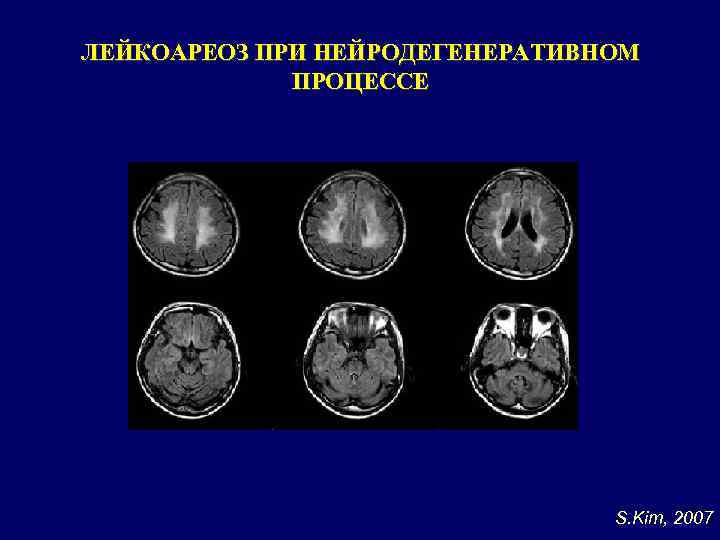

ЛЕЙКОАРЕОЗ ПРИ НЕЙРОДЕГЕНЕРАТИВНОМ ПРОЦЕССЕ S. Kim, 2007